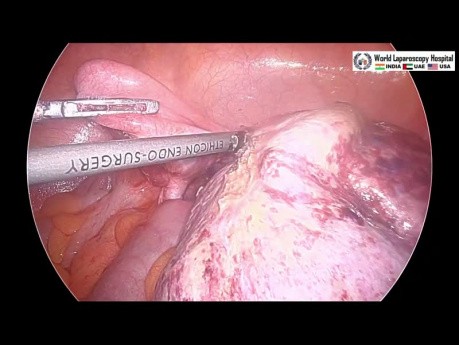

Ooforectomía laparoscópica presentando las tijeras HARMONIC ACE®+7 con hemostasia avanzada

Total Laparoscopic Hysterectomy featuring HARMONIC ACE®+7 Shears by Dr. Kondrup

Tijeras quirúrgicas HARMONIC ACE®+7

Ooforectomía laparoscópica presentando las tijeras HARMONIC ACE®+7 con hemostasia avanzada

Ethicon HARH23 Harmonic ACE+ 7 SHEARS with Advanced Hemostasis: 5MM X 23CM

Health Management and Leadership Portal, Bipolar coagulation laparoscopic scissors / bipolar cutting HARMONIC ACE® HAR23, HAR36 Ethicon Endo Surgery